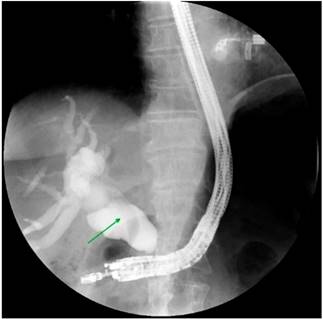

Con los hallazgos descritos se decidió el manejo paliativo y se llevó a CPRE con la intención de realizar una derivación biliar con stent; se encontró la papila distorsionada con retracción local de las paredes duodenales y se logró la canulación de la vía biliar distal, pero fue fallida para la vía biliar proximal. Entonces, se realizó la derivación biliodigestiva guiada por USE, en la que se encontró una infiltración neoplásica de la papila duodenal que impide su canulación y la cabeza del páncreas tenía una lesión hipoecoica heterogénea de 23 mm de diámetro con una dilatación retrógrada de la vía biliar hasta 18 mm (Figura 4). Se realizó una punción inicial de la masa para el estudio histológico y, posteriormente, de la vía biliar transduodenal con una aguja de 19 Fr, avanzando la guía hidrofílica 0,035; la dilatación se realizó con un balón dilatador biliar bajo control fluoroscópico y la posterior colocación del stent biliar metálico completamente cubierto de 10 x 80 mm, el cual se liberó bajo control endoscópico y fluoroscópico con una adecuada apertura y drenaje del medio de contraste y de bilis clara, sin complicaciones posteriores (Figuras 5 y 6). El reporte de la citología obtenida por endosonografía confirmó el compromiso por adenocarcinoma. A los 2 meses se le realizó control de bilirrubina total en 2,42 mg/dL; directa, en 1,85 mg/dL; e indirecta, en 0,58 mg/dL (Figura 7). La paciente continuó el manejo con oncología y cuidados paliativos.